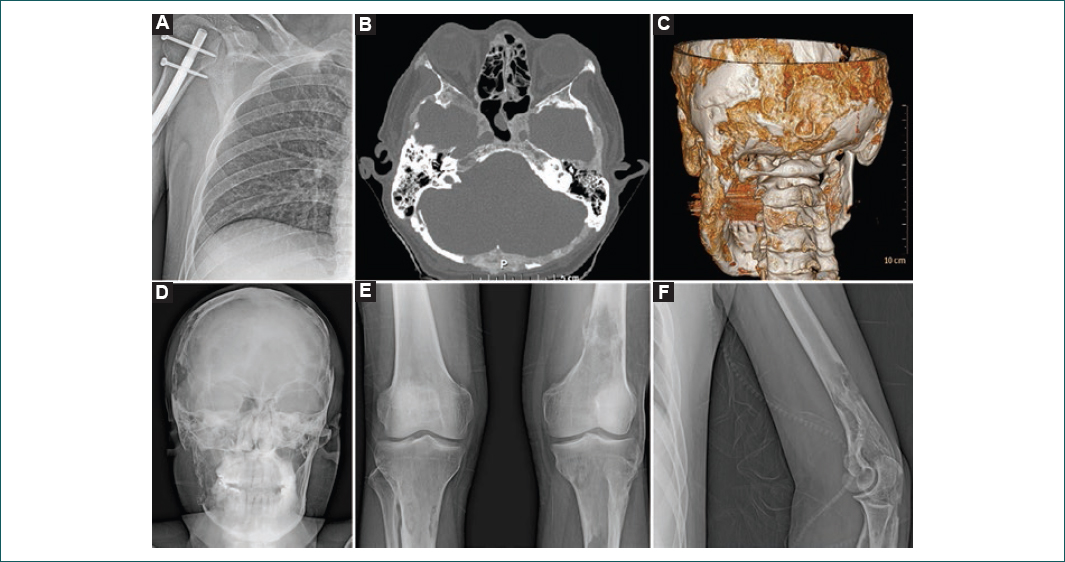

Varón de 35 años que ingresó al servicio de medicina interna con antecedente de infección por el VIH, diagnosticado 3 años antes de su ingreso, en tratamiento con tenofovir/emtricitabina y atazanavir, con última carga viral de 107 copias y CD4 de 132 células. Cuatro meses antes de su ingreso en medicina interna presentó, de manera súbita, una fractura del húmero derecho después de realizar un movimiento de sacudida, por lo que fue candidato a reducción abierta y fijación interna con material de osteosíntesis (Fig. 1 A). Tres meses después presentó una segunda fractura a nivel del hombro izquierdo, recibiendo tratamiento conservador con cabestrillo. Un mes después presentó fractura tibial derecha sin traumatismo asociado.

Durante el seguimiento por traumatología y ortopedia se observó la ausencia de consolidación, y además se encontró una protuberancia en la región occipital, fluctuante, no hipertérmica, con aumento progresivo de tamaño (Fig. 1 B y C). Se solicitó una serie ósea metastásica, que reportó lesiones líticas en el cráneo (Fig. 1 D), el tórax, ambos fémures y la tibia y el húmero izquierdos (Fig. 1 E y F), así como presencia de hipercalcemia grave (15.27 mg/dl). Al interrogatorio dirigido negó la presencia de fiebre, diaforesis, pérdida de peso o infecciones de repetición; refirió un adecuado apego al tratamiento antirretroviral, sin antecedente de infecciones oportunistas.

Ingresó a medicina interna para protocolo diagnóstico por hipercalcemia y fracturas patológicas. A su ingreso se documentó la presencia de síntomas CRAB (Calcium elevation, Renal dysfunction, Anemia, and Bone disease) de MM: calcio sérico de 16.7 mg/dl, elevación de creatinina sérica de 6.8 mg/dl, anemia con hemoglobina de 9.5 g/dl y evidencia radiográfica de lesiones óseas de aspecto lítico. Con esta sospecha se solicitó electroforesis de proteínas y cadenas ligeras, así como biopsia y aspirado de medula ósea. Se reportó electroforesis de proteínas urinarias con un pico en alfa-2 del 16.30% que no abarcaba toda la región, así como beta-2 microglobulina de 19.192 mg/l, sin pico monoclonal ni policlonal en banda gamma, con proteína de Bence Jones negativa. La determinación de las inmunoglobulinas séricas reportó: IgG 1960 mg/dl, IgA 271 mg/dl, IgM 249 mg/dl e IgE 12 U/ml. La biopsia de médula ósea informó hueso de aspecto poroso y consistencia pétrea, sin observar infiltración por células plasmáticas. El aspirado de médula ósea reportó un 6% de células plasmáticas de tipo I. Por lo anterior, se descartó la presencia de MM y de otras gammapatías monoclonales. Se midieron las concentraciones séricas de hormona paratiroidea PTH, que fueron de 3.1, y se descartó la presencia de un adenoma paratiroideo por ultrasonido. Continuando con el abordaje diagnóstico, se realizó un rastreo tomográfico que identificó múltiples lesiones líticas que presentaban expansión y destrucción de la cortical ósea en el cráneo, el macizo facial, la rama mandibular izquierda, ambos huesos ilíacos y el sacro (Fig. 1); crecimientos ganglionares cervicales a nivel II y III de tipo inflamatorio; e hígado, bazo, ambos riñones y páncreas con realce conservado al medio de contraste. Ante estos hallazgos se decidió solicitar una biopsia de hueso parietal, que reportó neoplasia maligna con extensa diferenciación plasmocitoide, sugiriendo un LPB. Finalmente, se solicitó un análisis inmunohistoquímico que reportó CD138+, CD20−, CD3−, CD30− y Ki-67 del 80%. Para aumentar la certeza diagnóstica se solicitó la revisión de laminillas, coincidiendo con el diagnóstico de LPB con expresión de CD138, MUM-1 y CD43, restricción de cadenas lambda, con índice de proliferación del 80% y asociado a VEB (CD20, CD3−, CD138+, CD30−, CL kappa−, CL lambda+, CD43+ y MUM-1+).